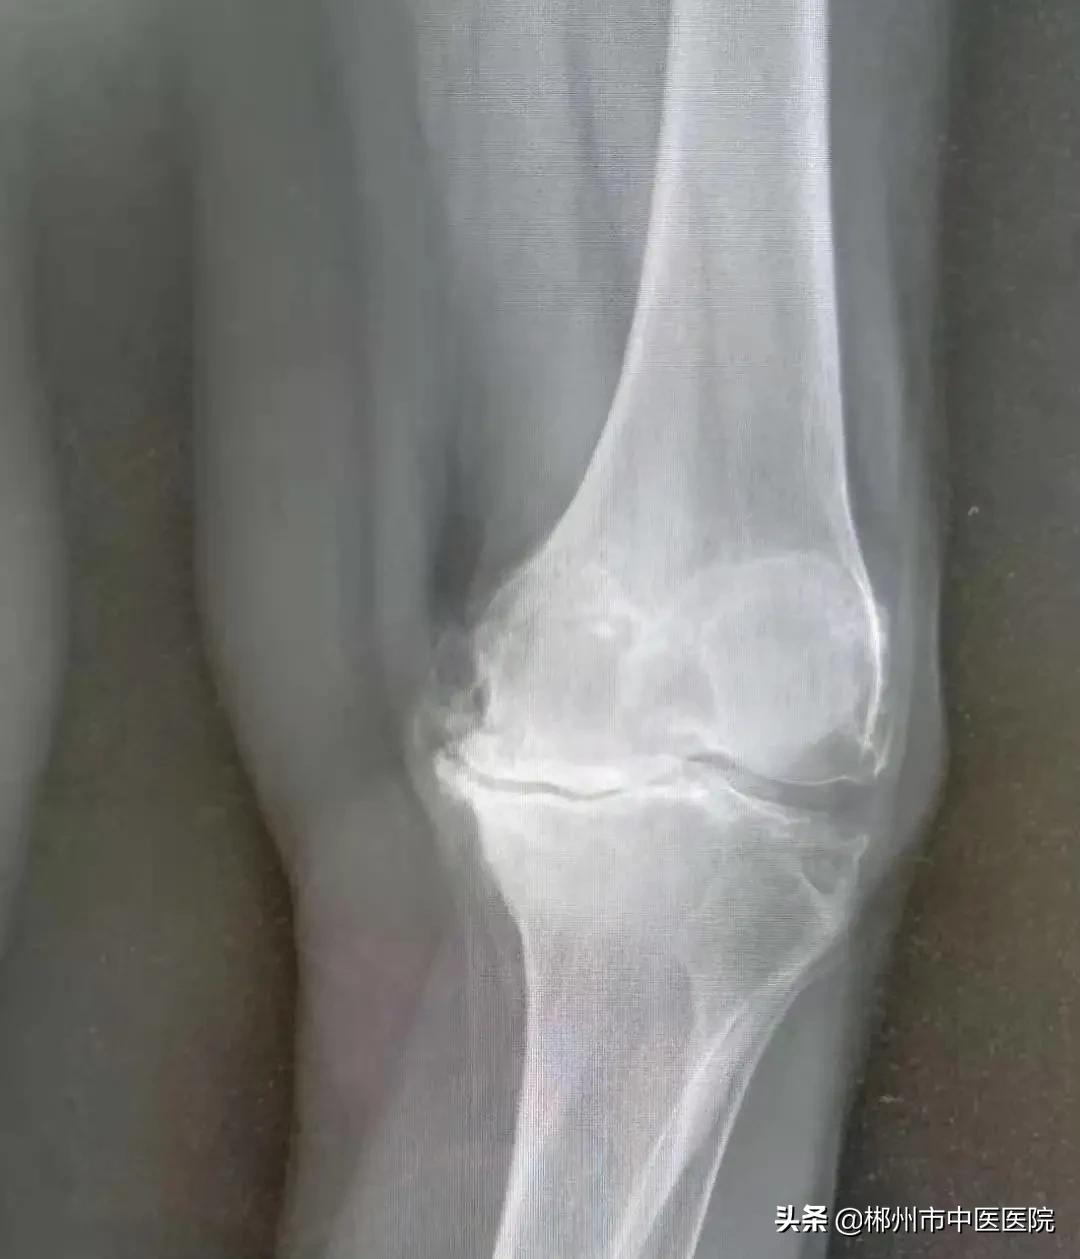

检查后发现李奶奶双膝关节肿胀、内翻畸形,左膝关节特别严重。

治疗前X线片情况